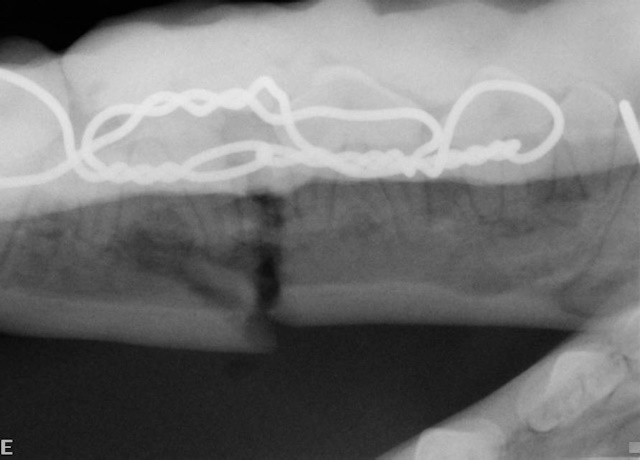

An intraoral cold cure composite splint is placed over the interdental wire to further stabilize the fractured jaw (image above). Intraoral radiograph showing the wire and composite splint. Notice the fracture gap even after careful placement of the wire and composite material (image below).